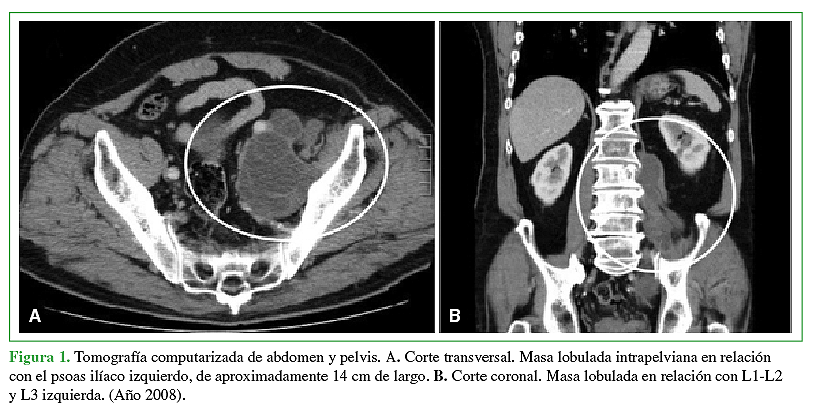

La hidatidosis es una enfermedad causada por el estado larval del platelminto Echinococcus, siendo la especie más prevalente Echinococcus granulosus. Es endémica Eurasia, Africa, Australia y Sudamérica. En Chile tiene una incidencia notificada de 2,1 casos por 100.000 habitantes y a pesar de que está asociada a las zonas ganaderas del sur de Chile, se presenta a lo largo de todo el territorio debido al desplazamiento de la población y su largo período de incubación. Se caracteriza por la presencia de un quiste habitualmente a nivel hepático (75%) o pulmonar (15%). La afectación de otros territorios es menos frecuente y el compromiso óseo es una rareza que no supera el 1 a 2,5%, ya sea en el tejido trabecular o canal medular. El tratamiento por lo general es médico-quirúrgico con resultados clínicos dispares debido a alta tasa de recurrencias y secuelas. La experiencia en el manejo de pacientes afectados con hidatidosis intrarraquídea es limitada debido a su baja frecuencia. Por ello quisimos reportar 2 casos observados en nuestro centro y analizar su manejo.Descargas